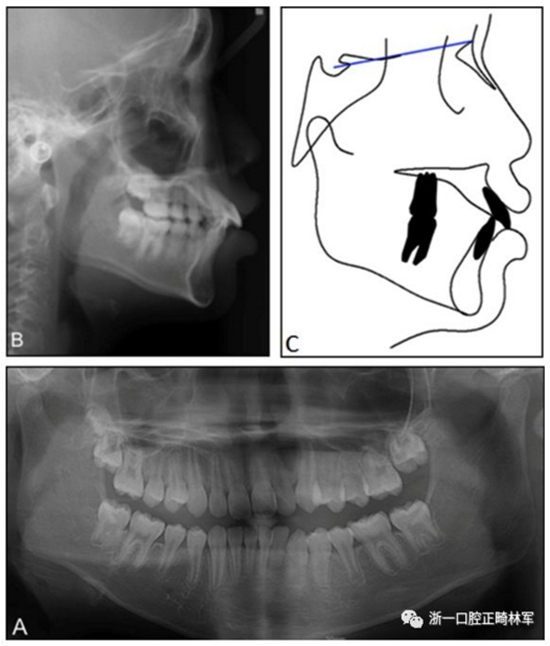

患者男,10歲11個(gè)月,主訴嘴突。側(cè)貌突面型,上下嘴唇凸起。開(kāi)唇露齒,上唇短。口內(nèi)示,中線齊,覆蓋7mm,II度深覆合,雙側(cè)磨牙關(guān)系I類(lèi),尖牙關(guān)系II類(lèi)。上頜牙弓輕度擁擠,下頜牙弓中度擁擠,spee曲線深,上頜第二磨牙未萌。

X線頭影測(cè)量分析示安氏I類(lèi)(ANB,3.5°;Wits,–1.5mm),低角型(FMA,23),上下頜切牙前傾(U1-FH,121°,IMPA,96°)。